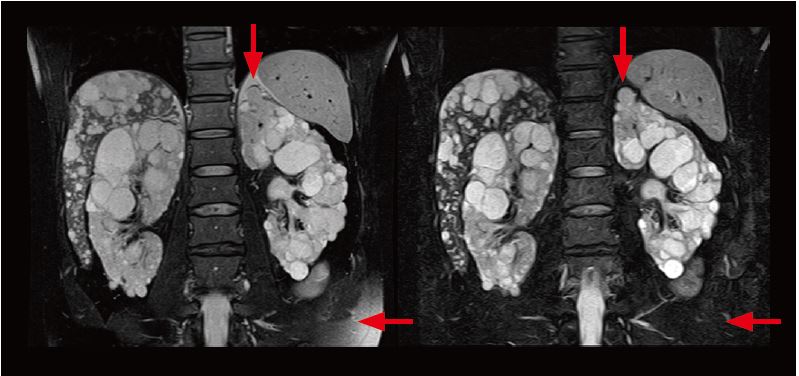

На рис. 3 наведено клінічний випадок полікістозу нирок. Нерівномірне придушення жиру іноді спостерігається на Т2-зважених зображеннях з придушенням жиру в черевній порожнині, але при використанні WFS DIXON жир пригнічується з високою точністю. Краї ураження чітко зображені, що полегшує отримання точних вимірювань об’єму функціональної області нирок.

Рис.3. Порівняння Т2-зваженого зображення з придушенням жиру (ліворуч) і зображення води (праворуч). На зображенні води жир у черевній порожнині ефективно пригнічується з високою точністю (стрілки).